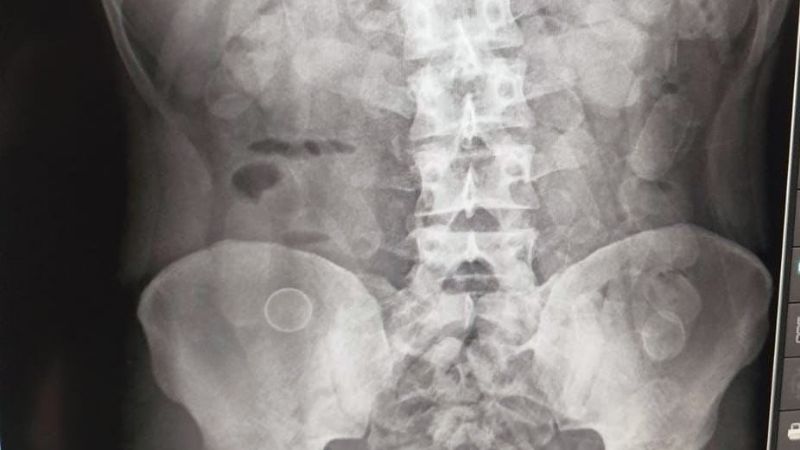

Ante la alerta del can, los gendarmes tomaron contacto inmediato con la Unidad Fiscal Federal de Jujuy, lo que permitió intensificar los controles y trasladar a los involucrados al hospital local. Mediante estudios de Rayos X, se confirmó que ambos poseían cuerpos extraños en sus abdómenes.

Tras la evacuación médica, se constató que los hombres habían ingerido: 95 y 89 cápsulas cada uno. Un total de 184 cápsulas de clorhidrato de cocaína con un peso total de 2 kilos y 168 gramos.